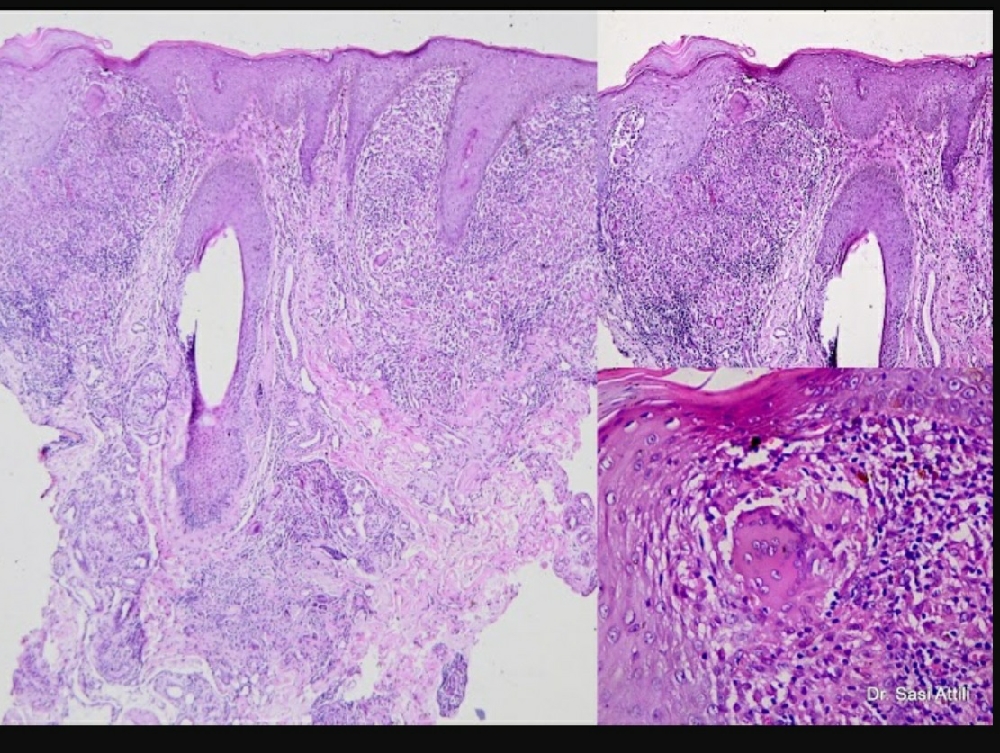

> go to the image library. Web cutaneous tuberculosis images. Web the patient was diagnosed with the lupus vulgaris (lv) form of cutaneous tuberculosis (tb). Web complicating the picture, several skin conditions that are separate and distinct from lupus erythematosus make use.

Lupus Vulgaris Bilder - Web complicating the picture, several skin conditions that are separate and distinct from lupus erythematosus make use. Web cutaneous tuberculosis images. > go to the image library. Web lupus vulgaris is the most common paucibacillary form of cutaneous. Web the patient was diagnosed with the lupus vulgaris (lv) form of cutaneous tuberculosis (tb).